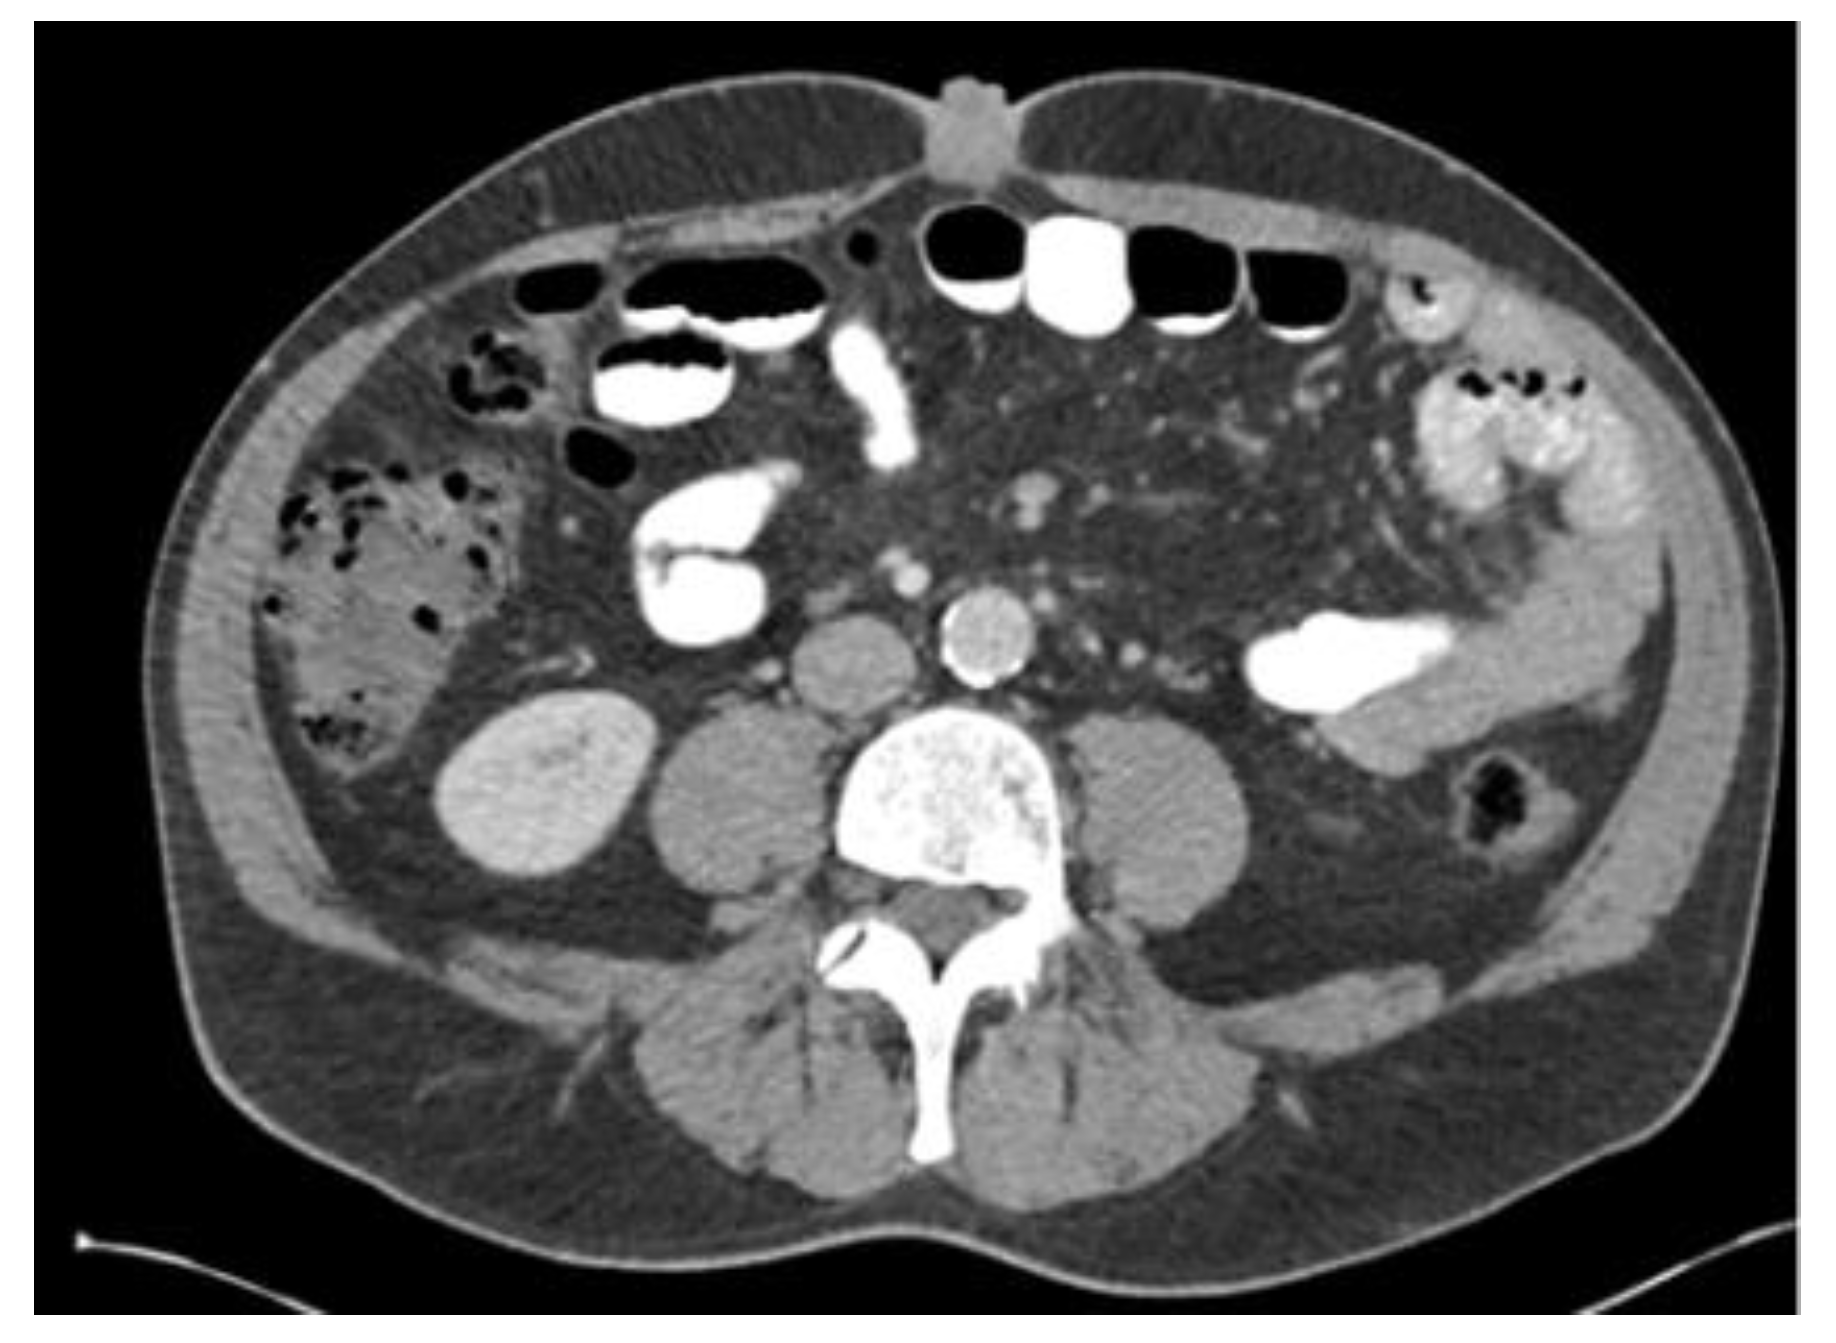

In preparation for the procedure, it was noted that the patient had endorsed lethargy over the past few weeks. Additionally, preprocedural routine labs were notable for a direct bilirubin of 2.93 mg/dL. Due to the polypoid and irregular nature of the lesion, his concomitant lethargy, and direct bilirubinemia, a CT scan of the patient’s abdomen and pelvis was performed, which revealed a distal intrahepatic cholangiocarcinoma with involvement of left hepatic lobe (Figure 1) and umbilical induration corresponding to the skin lesion (Figure 2). A magnetic resonance cholangiopancreatography (MRCP) was performed for further characterization of the cholangiocarcinoma, which revealed an intrahepatic cholangiocarcinoma (Figure 3).

Figure 1. CT scan showed a distal intrahepatic cholangiocarcinoma with involvement of left hepatic lobe .